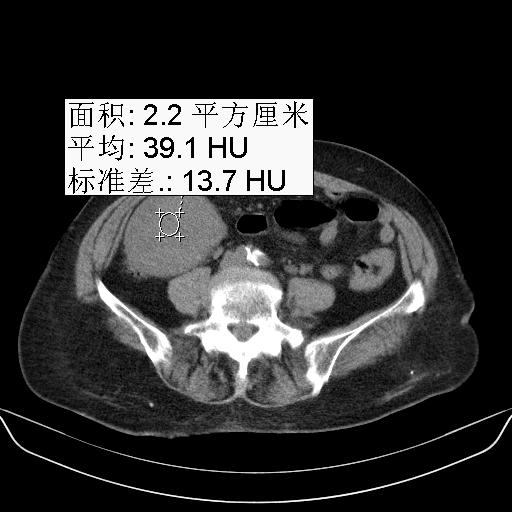

以下是引用yuhongjun在2010-3-12 6:32:00的发言:[br]回肠末端间质瘤,不除外阑尾粘液囊腺瘤,臀部注射性肉芽肿钙化. [br] [br]